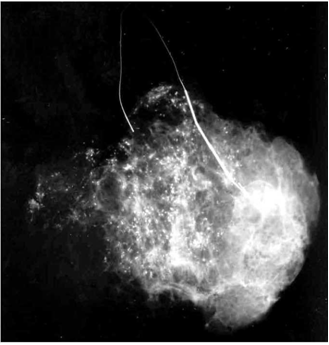

כיום מקובל להכניס מספר סימונים על ידי תיל לסימון מרחב הנגע בשד ולא רק את מרכזו, ובכך להגדיל את הסיכוי להוציאו בשלמותו. לאחר הביופסיה מבצעים צילומי ממוגרפיה של רקמת השד שהוצאה, ומוודאים שהנגע אכן הוצא בשלמותו (תצלום 28.12).

כריתה בלתי שלמה מחייבת כריתת שוליים רחבים יותר של רקמת השד להשלמת הניתוח. רצוי לבצע צילום רנטגני של התכשיר כשהחולה עדיין בחדר הניתוחים, כדי להימנע מניתוח חוזר במועד מאוחר יותר.

ביופסיה במחט עבה: בביופסיה זו משתמשים במחט מיוחדת (איור 16.12) המורכבת משתי מחטים, האחת בתוך השנייה. המחט הפנימית היא מחט בעלת חוד שבהמשכה קיימת מגרעת, והמחט החיצונית הנעה על המחט הפנימית מסתיימת בקצה בחלק מושחז כסכין. המחט על שתי מרכיביה מוחדרת עד הנגע. בשלב זה, המחט הפנימית נדחפת לתוך הנגע ומכיוון שרקמות הן בדרך כלל אלסטיות, קטע מרקמת הנגע ממלא את המגרעת במחט הפנימית. בשלב הבא המחט החיצונית נדחפת וחותכת אל הרקמה אשר מילאה את המגרעת במחט הפנימית. המחט כולה מוצאת כאשר בתוכה גליל רקמה שנשלח לבדיקה פתולוגית. כיום, כל סדר הפעולות הזה אינו מבוצע ידנית אלא באמצעות מכשיר מיוחד הנקרא "אקדח" ביופסיות, המבצע את פעולת החדרה המחט לנגע והחיתוך באופן אוטומטי. ככל שקוטר המחט גדול יותר, ומספר הגלילים הנלקח גדול יותר, אמינות הבדיקה גבוהה יותר. מספר עבודות הראו התאמה של 80% ל-97% בין הבדיקות של הגלילים לביופסיה הכירורגית. האמינות הגבוה יותר מדווחת כאשר בהכוונת מחט הביופסיה נעזרו ב- US או בממוגרפיה. במידה ולא ניתן למשש את הנגע, אפשר להיעזר בהכוונת ה-US או הממוגרפיה (ממוטומיה או ביופסיה סטריאוטקטית) כדי להביא את מחט הביופסיה לנגע. פרטי הטכניקה מתוארים בפרק הקודם. את החומר המוצא בממוטומיה מצלמים כדי להוכיח שאכן הוא מכיל את ההסתיידויות שרצינו לדגום (תצלום 31.12).